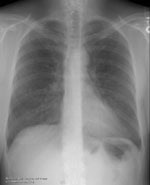

The initial chest radiograph demonstrated multiple small nodular densities in the lungs. The soft tissue defect from the breast carcinoma is best appreciated on the lateral view, but some soft tissue asymmetry is also evident on the PA exam. (Click on the small images to view the larger radiographs)

PA: